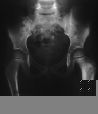

Radiología Caso 3

Caso 3

Case 3